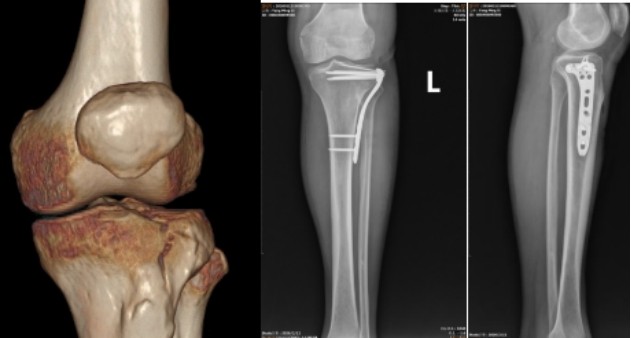

微创关节线入路技术可聪明多啦。它是沿着膝关节的生理结构来设计切口的,就像给钥匙找到了最合适的锁孔一样精准。通过横断髂胫束,直接把关节面显露出来,让医生能清楚地看到骨折的地方。在手术过程中,医生会用细克氏针“竹筏排技术”,对塌陷的软骨下骨进行多点支撑复位。这就好比给一个凹凸不平的地面重新铺上平整的地砖,让关节面恢复解剖对位,这样就能有效避免术后关节面下沉,为膝关节功能的恢复打下坚实的基础。打个比方,如果关节面就像一个桌子的桌面,骨折后桌面变得凹凸不平,这个技术就是把这个桌面重新打磨平整,让桌子又能稳稳地使用啦。

这项技术还有一个很大的优点,就是微创。它的切口只有数厘米长,而且巧妙地隐藏在关节线皮肤褶皱处。等伤口愈合后,疤痕几乎看不出来,这对于那些爱美的人来说,可真是个好消息。在手术中,医生会采用“吊线技术”来扩大视野,就像在黑暗的房间里打开了一盏灯,让医生能看得更清楚,操作起来也更方便。在Gerdy结节处精准分离,能最大限度地保留骨膜、肌肉、韧带等软组织的完整性。传统手术就像是一场“暴力拆迁”,大面积剥离软组织,破坏了局部的血供;而这个微创技术就像是一个细心的“装修师傅”,小心翼翼地保护着周围的“设施”,从源头上降低了切口感染、皮瓣坏死、内固定物外露等并发症的风险。